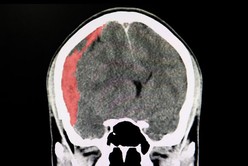

Diego Armando Maradona, actual entrenador de Gimnasia, arribó este martes por la tarde a la Clínica Olivos, donde será sometido esta noche a una cirugía a raíz de un hematoma subdural en la cabeza, luego de permanecer internado en un centro de salud de la ciudad bonaerense de La Plata.

Diego Maradona será operado por un edema en la cabeza